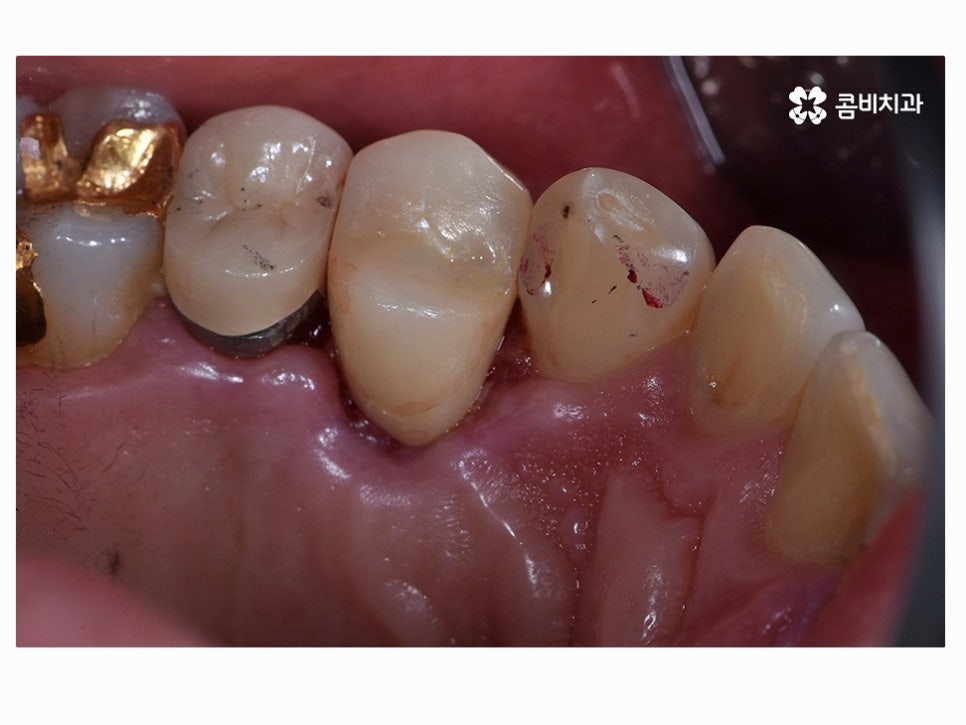

마지막으로 소개드릴 사례 역시도 이미 크라운을 씌웠던 치아 내부가

심하게 썩어서 잇몸 치료와 함께 지르코니아 크라운을 다시 씌운 사례라고 할 수 있어요.

이러한 사례처럼 이미 기존 치아의 형태가 심하게 손상이 된 경우에는

치료가 쉽지 않고 발치로 이어지는 경우도 많지만 환자분 들께서도

대부분 자연치아를 살리길 원하시고 명동치과 의사의 입장에서도

되도록 자연치아를 되도록 오래 쓰실 수 있도록 도와드리고 있는데요.

기존의 치아를 최대한 살려도 치료 후 수명이 오래가지 못할 것으로

예상이 된다거나 어쩔 수 없이 발치를 할 수밖에 없는 상황도

있기 때문에 나이가 들수록 치아 검진 습관을 더욱 강조되고 있어요.

다행히도 사진의 환자분께서는 내부 충치를 잘 제거하고

다시 지르코니아 크라운을 씌워서 치료를 안전하게 마칠 수 있었지만

나이가 들수록 잇몸질환이 잦아질 수 있고 그로 인해 잇몸이

내려앉으면 치아의 하단부가 시리거나 크라운 치료를 했던

부위와 기존 치아와의 틈이 발생하는 경우가 종종 있는데요.